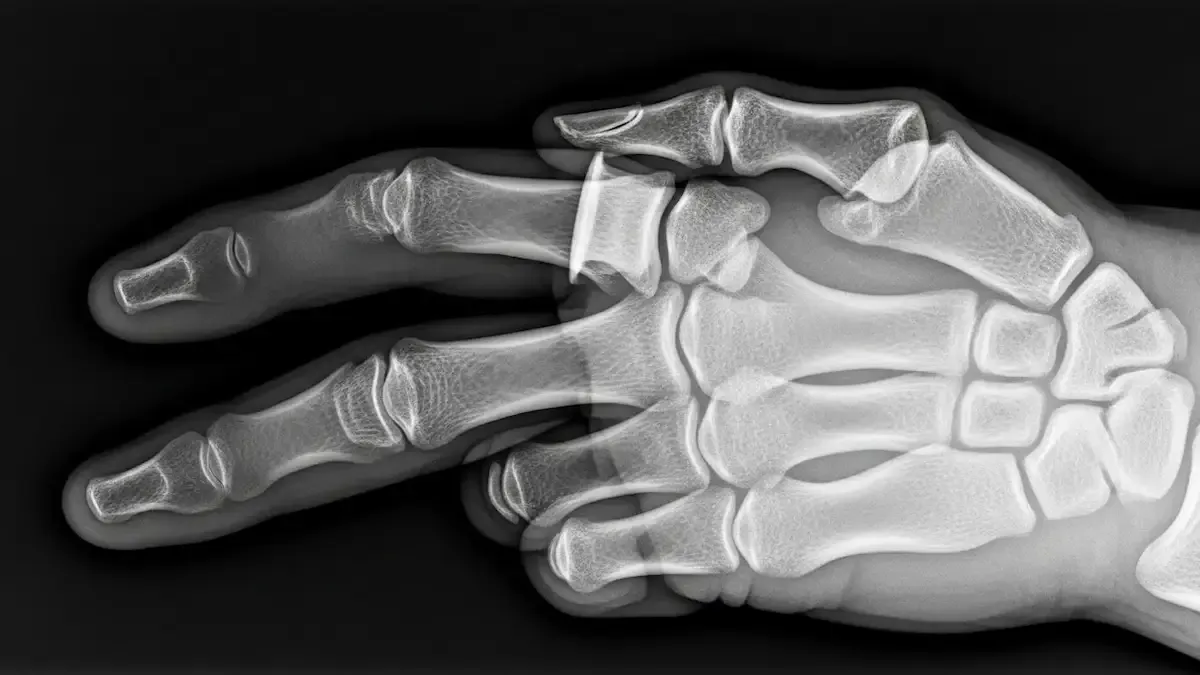

O tumor glômico origina-se do corpo glômico, uma estrutura neuromioarterial especializada em termorregulação.

Dados internacionais mostram que 75% desses tumores ocorrem na mão, sendo 65% localizados na região subungueal.